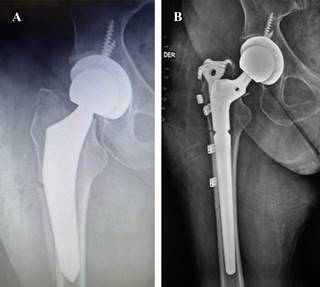

Postoperative fractures can result from direct trauma and should be treated according to the classification and management of periprosthetic fracture protocols. Some non-identified fractures could be produced during the procedure and present in the former days as complex, unstable fractures with stem compromise, minor or severe subsidence that could need former revision and stem removal and exchange (Figure 8).